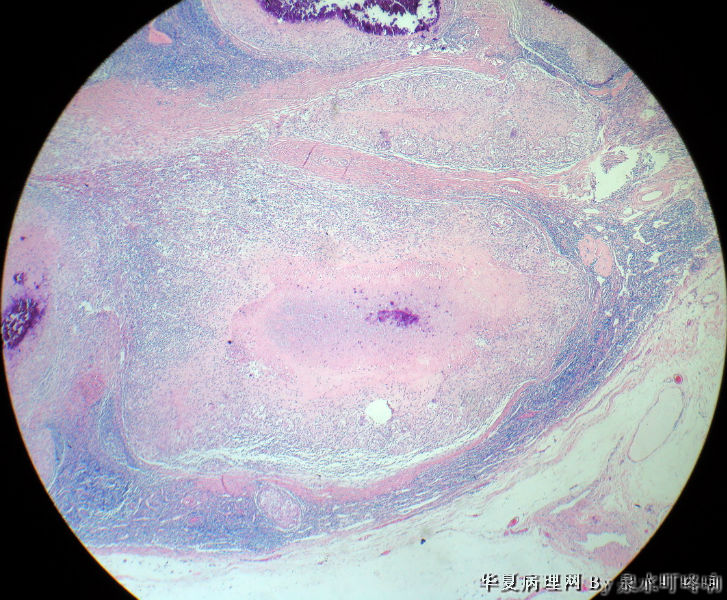

女,3岁,主因左腋窝肿物半年,术中见为肿大淋巴结,淋巴结内有脓液及坏死组织。

大体:灰红色组织一块,大小约4.6×3.5×2厘米,切面可见两个囊性区域,内容乳白色浓稠液体。